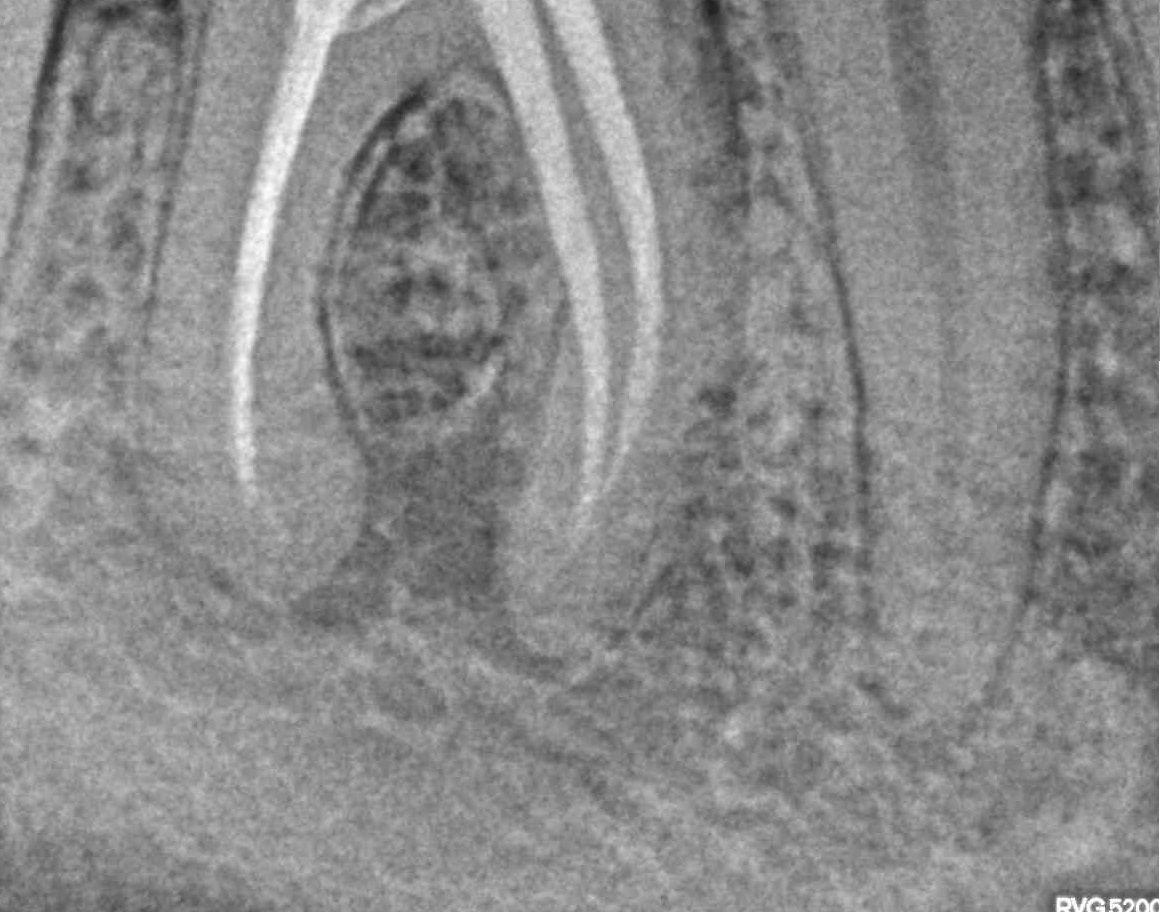

- Лечение периодонтита

Проблема

Пациент обратился в клинику с постоянными ноющими болями усиливающимися при накусывании.Решение

В нескольких клиниках было предложено удаление данного зуба. В нашей клинике такие зубы лечат. Пациенту было проведено эндодонтическое лечение данного зуба. Результат положительный, идет восстановление костной ткани.Оставьте заявку - перезвоним в течении 15 минут!